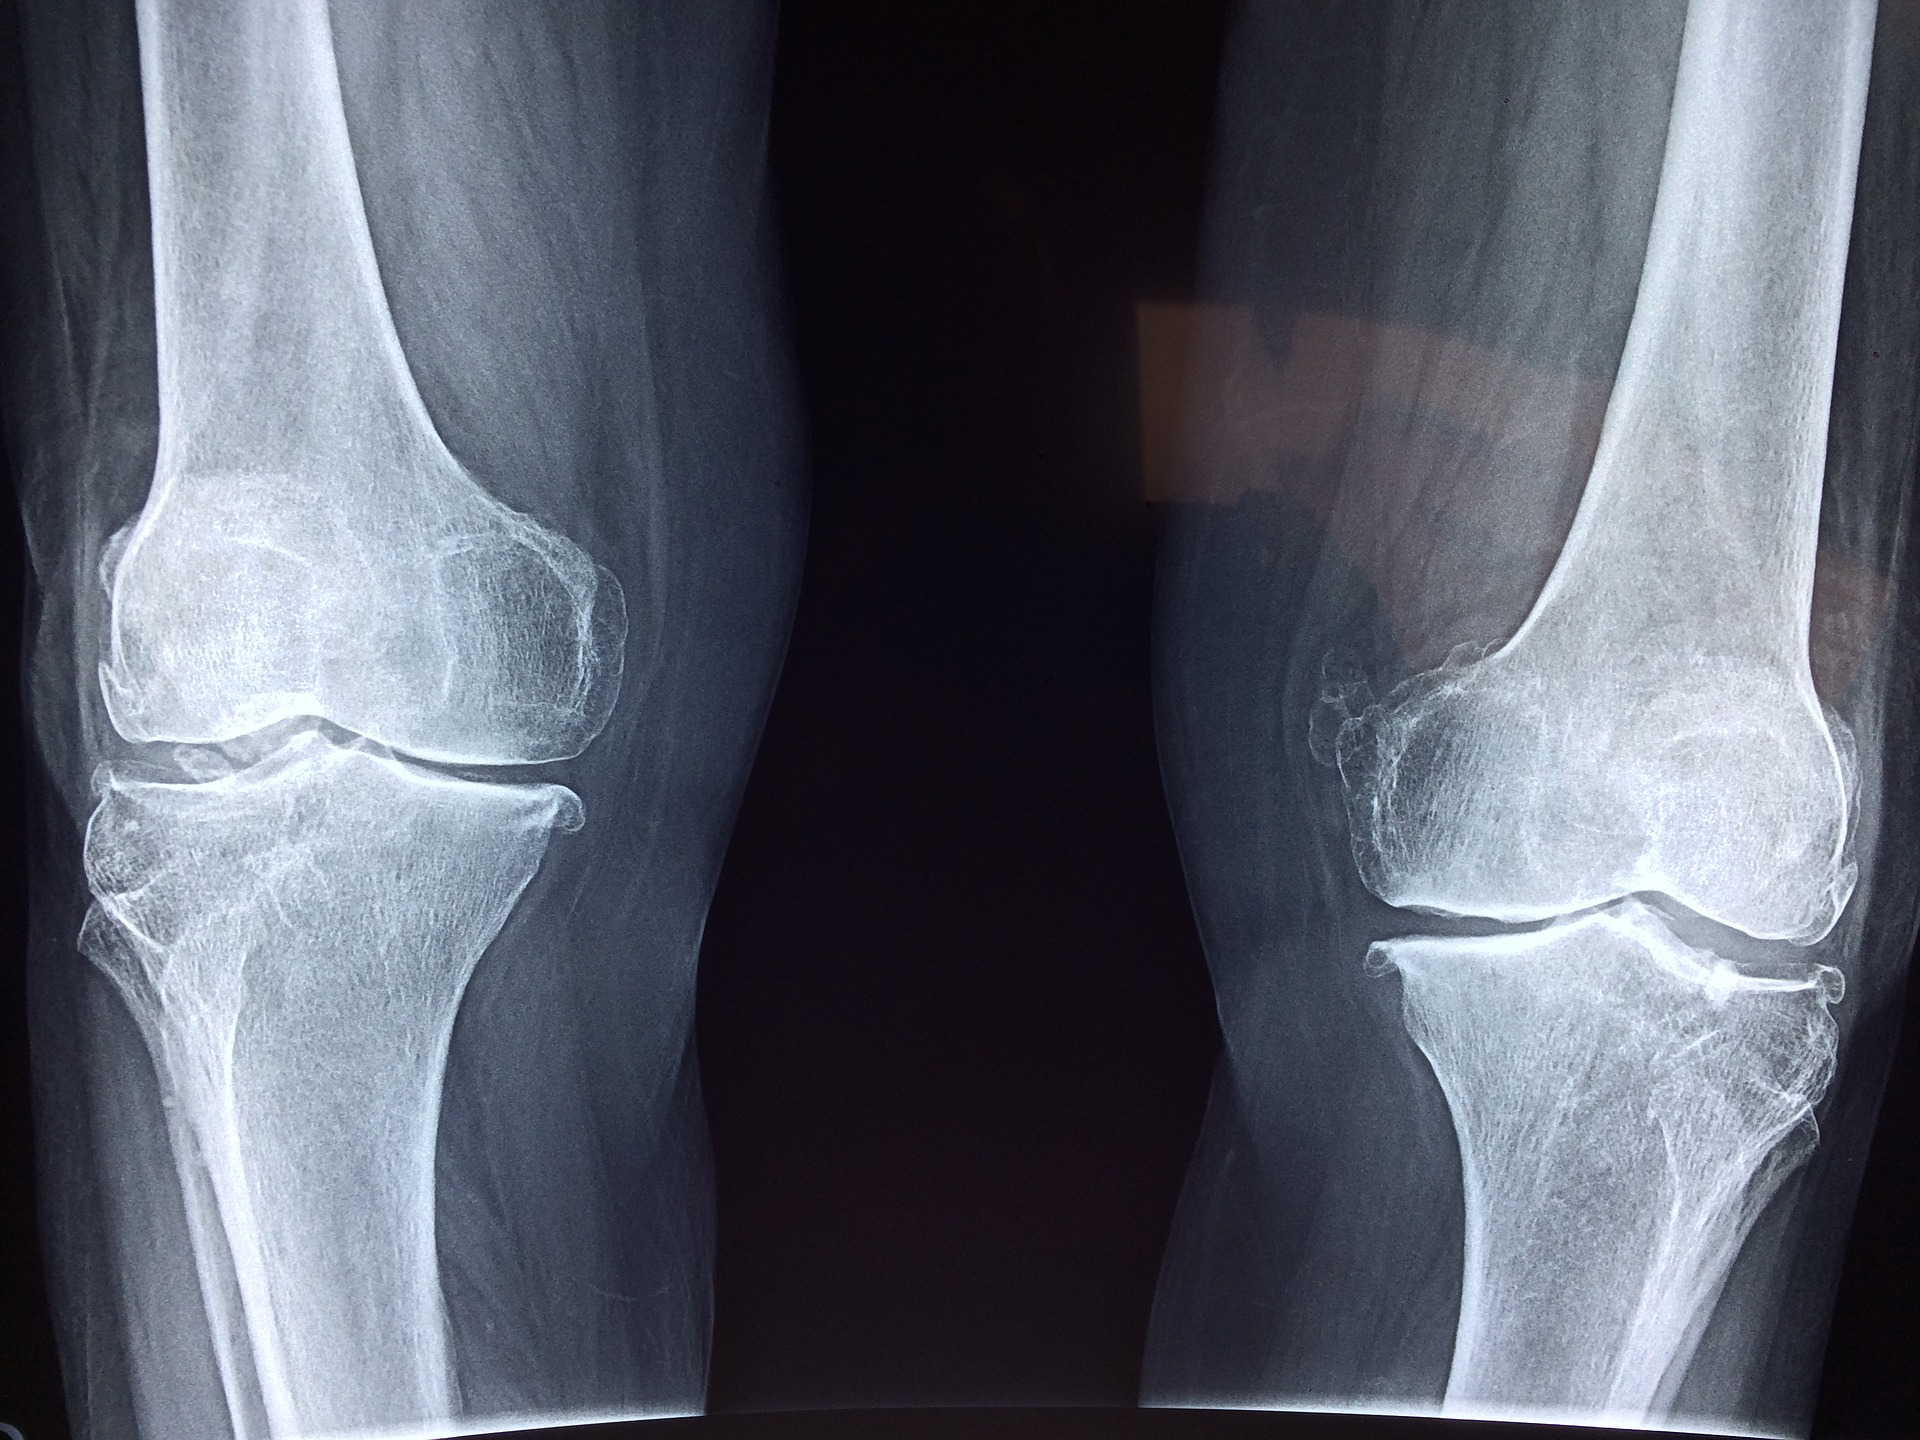

In a new study published in JAMA Network Open, a team from UT Health Austin’s Musculoskeletal Institute found that a decision aid powered by artificial intelligence (AI) can help patients and their doctors determine which course of treatment for osteoarthritis of the knee is most appropriate to improve health outcomes, according to a news release from UT Health Austin.